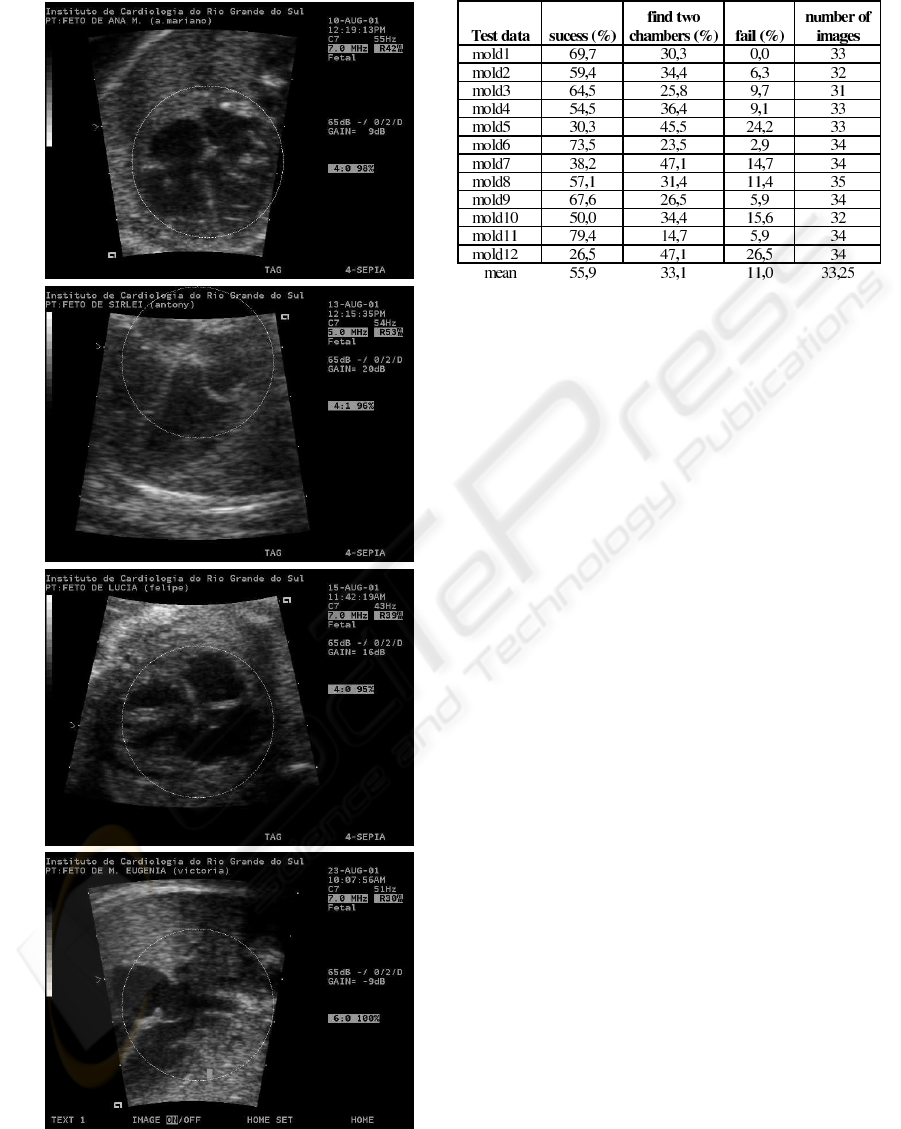

Figure 8: Trial obtained, only mean.

graphic images. Considering the graphic depicted in

Figure 8 and the class ”find two chambers” as ob-

jective, we can confirm the success of the proposed

method.